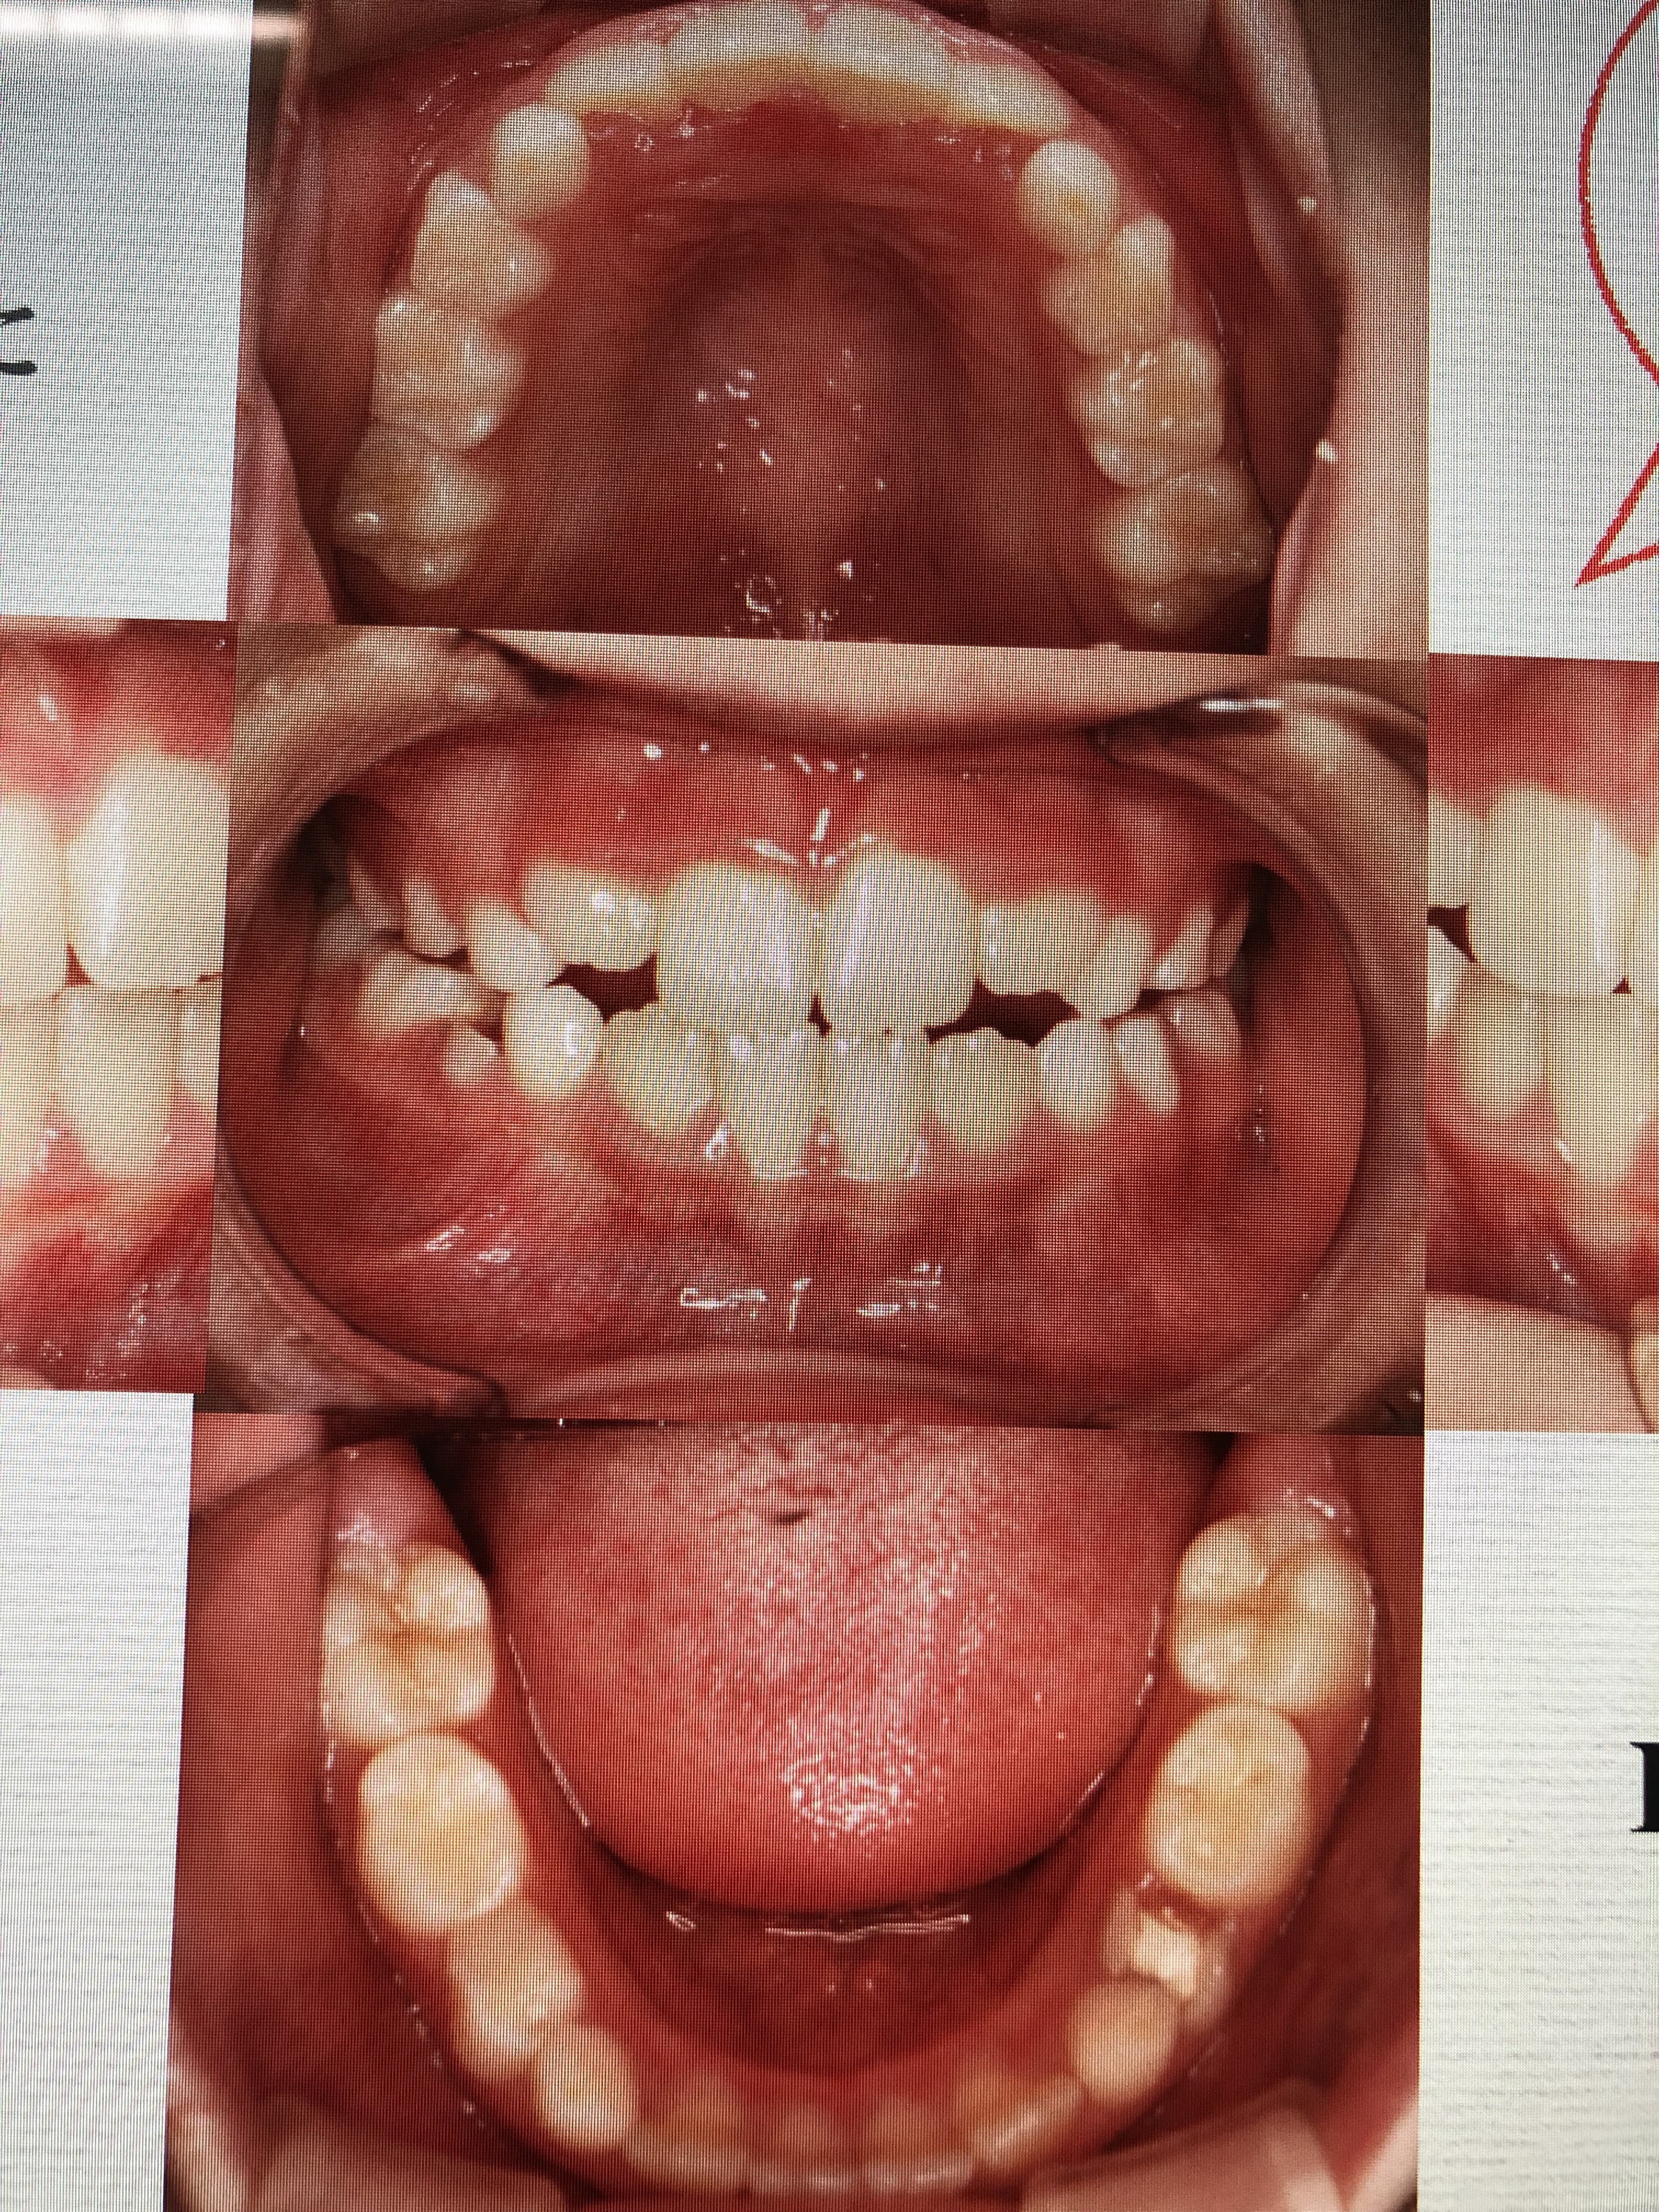

また、当院のMRC担当でも有ります、衛生士からも症例発表をさせて頂きました。小児の健康や歯並びの改善を目的とするMRCシステムを取り入れて、約2年ほどが経ちました。今では、多くの子供達が健全な口腔環境、成長を目的に当院に来院される様になりました。

健全な口腔環境を整える上では、呼吸のバランスや舌の位置、口腔周囲の筋肉の使い方などを日々のトレーニング(アクティビティー)によって正常な状態に改善する事は必要不可欠です。

日頃何気なく行っている’癖’が、良い習慣に変化出来る事で、口腔内の環境は劇的に変化して行きます。当院で行なったMRCの症例写真が物語っていると思います。